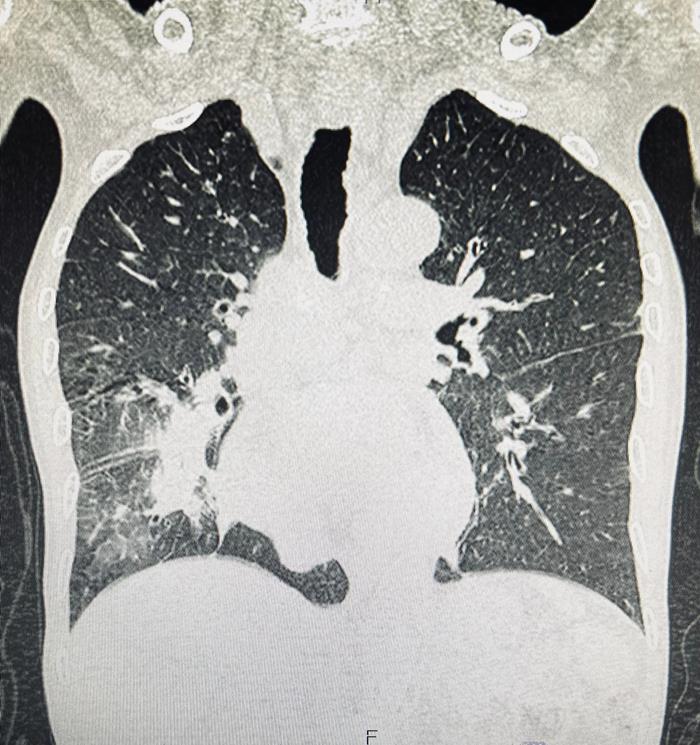

ผู้ป่วยรายนี้เป็นเพศชาย วัย 70 ปี มาด้วยอาการไอเรื้อรัง มีเสมหะปนเลือด หอบเหนื่อยจนเดินไม่ค่อยไหว ผอมจนน้ำหนักลด เมื่อเอกซเรย์ตรวจดู พบว่า มีลักษณะคล้ายปอดอักเสบที่ด้านขวาล่างหรือมีอะไรที่คล้ายก้อนมะเร็งอยู่ตรงนั้น

เกิดปอดแฟบอย่างที่เห็นในฟิล์มที่คล้ายลักษณะก้อน ๆ